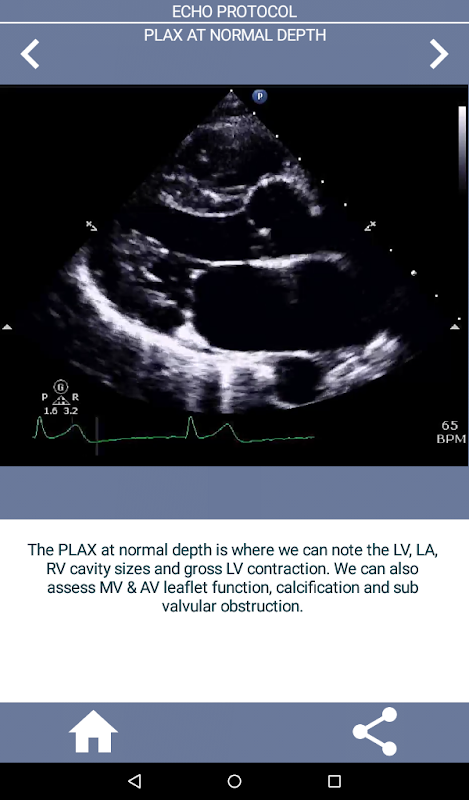

শুধু ইকোকার্ডিওগ্রাফি শিখতে শুরু করছেন নাকি সেই ইকো চাকরির ইন্টারভিউয়ের জন্য দ্রুত রিফ্রেশার প্রয়োজন? এই অ্যাপটি আপনাকে একটি বড় হাসপাতালে বর্তমানে ব্যবহৃত ইকো টেকনোলজিস্টের দৃষ্টিকোণ থেকে সম্পূর্ণ TTE প্রোটোকলের গতিতে দ্রুতগতিতে এগিয়ে নিয়ে যাবে এবং সেইসঙ্গে স্টার্টিং কার্ডিয়াক সোনোগ্রাফারকে একটি সম্পূর্ণ ইকো পরীক্ষার জন্য একটি সংক্ষিপ্ত, বিস্তারিত "কীভাবে" নির্দেশিকা প্রদান করবে। . অ্যাপটিতে 90% এরও বেশি ভিডিও ক্লিপ রয়েছে যা সঠিক ভিউ প্রদর্শন করে এবং সবচেয়ে সাধারণ অস্বাভাবিক কার্ডিয়াক প্যাথলজি (যেমন অ্যাওর্টিক স্টেনোসিস) দেখায় যা একটি ইকো প্রযুক্তির সম্মুখীন হতে পারে এবং কী করতে হবে।